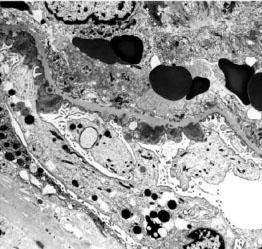

光镜下,大多数患者肾小球呈内皮细胞、系膜细胞弥漫性急性增殖,少数以渗出病变为主,另有少部分呈系膜、毛细血管型病变(膜增殖型病变),严重时增生的系膜可将肾小球分隔成小叶状,偶有球囊新月体形成。电镜可见上皮下电子致密物呈驼峰状沉积,为本病的特征。但这一变化消失较快,发病3个月后即不易见到,这些沉积物多在上皮侧,有时在内皮下。免疫荧光检查,内含有免疫球蛋白,主要是IgG、IgM、IgA也可见到,同时也可有C3沉积,有时尚可见到链球菌抗原在系膜区沉积物中。见图2—1、图2—2、图2—3。

图2—2 毛细血管内增生性肾小球肾炎,上皮下有驼峰状电子致密物沉积(电镜 x6800)